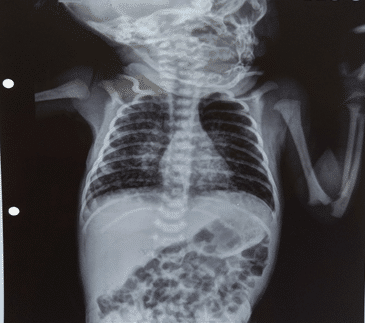

Chest X-rays of a 14-year-old male (BCG-vaccinated) with a positive tuberculin skin test and dextrocardia. Pneumonic infiltration was detected at the follow-up in the right lower zone of the chest X-ray after 50 days of isoniazid treatment

BCG (Bacille Calmette-Guérin) vaccine is a vaccine that is used to protect against tuberculosis. This vaccine is not widely used in the United States. However, it is often given to infants and small children in other countries where TB is common. It primarily affects the lungs but can also infect other parts of the body, such as the lymph nodes, bone, and brain.

The BCG vaccine is not effective in preventing TB, but it can significantly reduce the risk of infection and TB disease, particularly in children. It is essential in areas with a high prevalence of TB, as it can help to reduce the overall incidence in the population. In addition to its role in preventing TB, the BCG vaccine may also have some non-specific effects on the immune system, which may provide some protection against other infections.